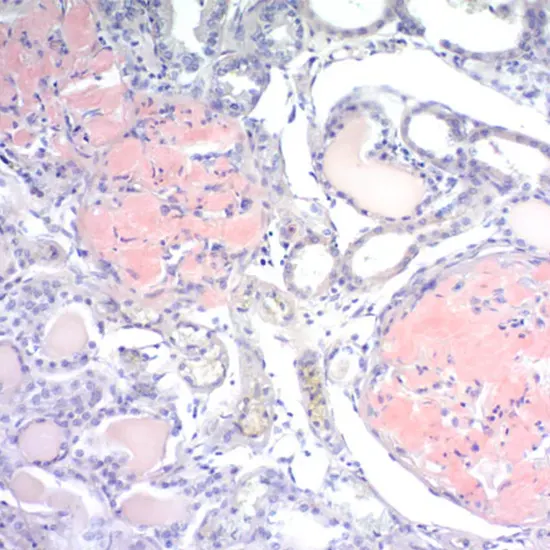

One of the main techniques for identifying the amyloid structure of protein aggregates is Congo Red dye (CR) staining. The amyloid nature of protein aggregates cannot be confirmed by CR staining, as evidenced by several tests.

The amyloid protein has an apple-green birefringence when illuminated by polarised light and is salmon-pink in c stained with congo red on tissue. Amyloid fibril deposits are thought to be pathognomonic for this apple-green birefringence.

• Under the on-polarized light, Congo red exhibits red-orange deposits; for specificity, apple-green birefringence under polarised light is needed.

• Collagen, fibrin, or other protein deposits may exhibit non-specific red Congo red staining; collagen is occasionally refractile but not frequently green. African Red

• In contrast to fibrillar collagen, only Congo red Red without polarisation causes amyloid fibrils to become birefringent (also called "congzoophiliaAlthough congophilic, elastic fibres are not birefringent.